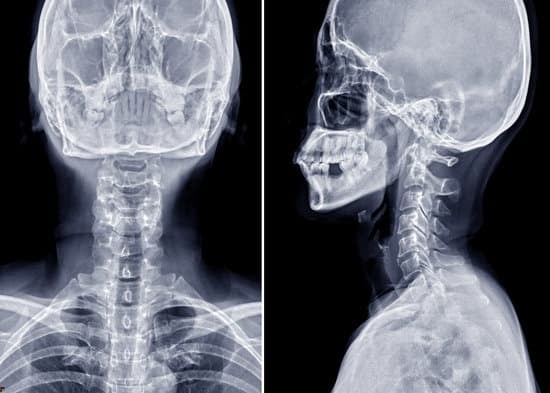

경추 디스크 X-ray (방사선 검사): 목적과 절차

정면 및 측면 촬영

정면 촬영: 목뼈의 좌우 정렬 상태와 척추 사이 간격을 확인합니다.

측면 촬영: 목의 전만(정상 곡선)과 척추 간의 높이를 평가합니다.